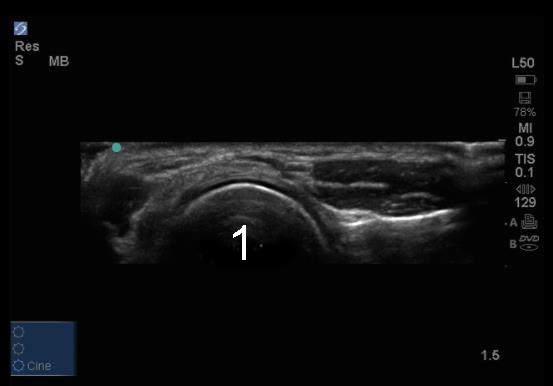

Codo: Fosa posterior, vista transversal - Imagen

Cabeza radial